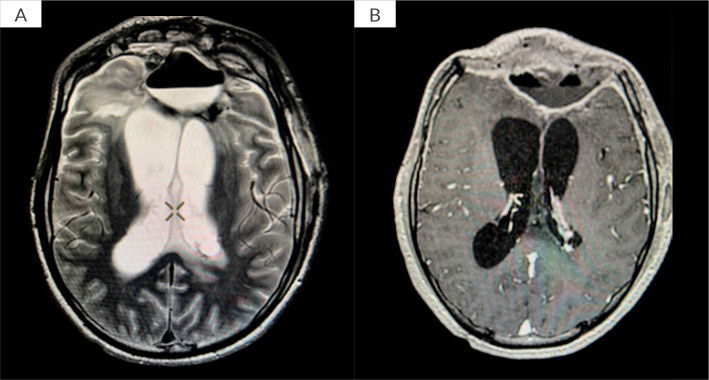

Case description: We present two cases of brain abscess treated at a tertiary care centre using continuous abscess cavity irrigation after conventional interventions proved insufficient. The first patient, a 15-year-old male, experienced recurrent MDR brain abscesses despite multiple surgical procedures and broad-spectrum antibiotics. Initiation of continuous irrigation, combined with targeted antimicrobial therapy, resulted in rapid clinical stabilisation and marked radiological improvement, with minimal long-term sequelae. The second patient, a 65-year-old female, developed multiple brain abscesses after traumatic brain injury and decompressive surgery. Although continuous irrigation effectively controlled the intracranial infection and imaging confirmed resolution, her neurological recovery was limited due to profound pre-existing brain damage.